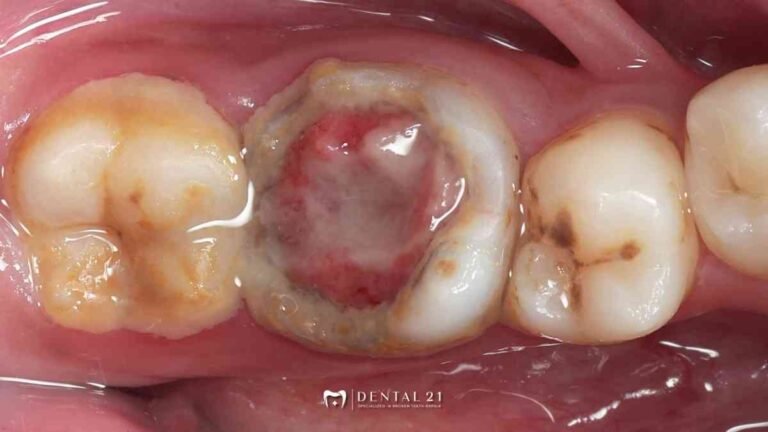

Dentist PIK untuk Gigi Rusak Parah: Tambal, PSA, atau Crown? Ini Cara Menentukannya Saat Anda mencari dentist PIK untuk menangani gigi rusak parah, sering kali muncul pertanyaan: apakah kondisi ini cukup ditambal, perlu PSA (perawatan saluran akar), atau bahkan memerlukan…